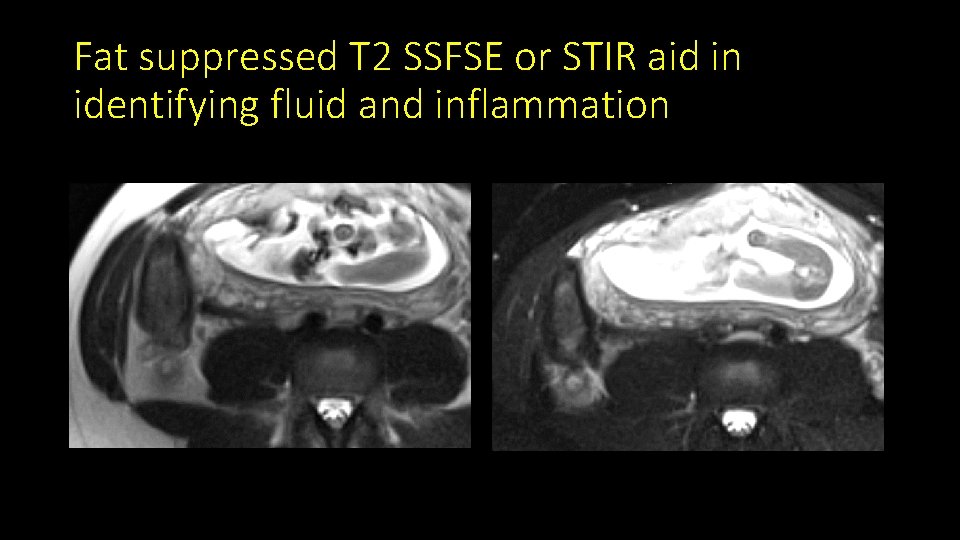

Fat suppressed T 2 SSFSE or STIR aid in identifying fluid and inflammation